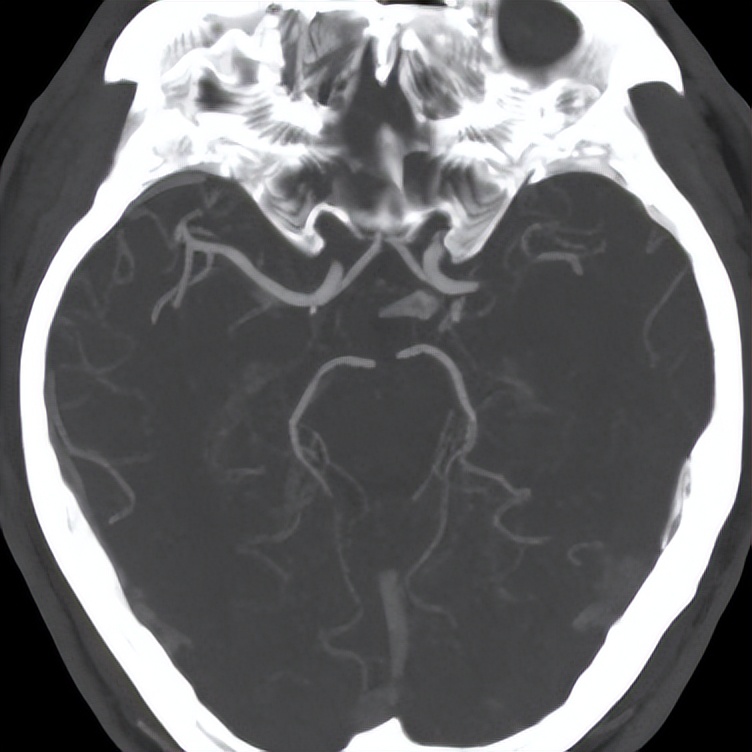

颅脑CT排除颅内出血;(5)颅脑CT未出现大面积脑梗死早期征象;(6)影像学检查(CTA、MRA、DSA)证实脑部大动脉闭塞;(7)年龄在18岁至80岁之间;(8)患者或者家属签署相关同意书。

缺血性脑卒中是由区域脑血流(CBF)突然持续减少导致细胞死亡引起的,而受损组织的周围区域可能会随着区域脑血流(CBF)的突然恢复而恢复,即半暗带,半暗带是围绕着不可逆损伤的核心的一个电不兴奋的、灌注不足的实质区域。所以急性缺血性卒中治疗的主要目标是通过重新开通闭塞的大脑供血动脉和再灌注缺血半暗区来抢救缺血但仍有活力未坏死的脑组织。因此在有效的时间窗内开通血管、恢复血流、抢救缺血半暗带区域细胞功能是本病成功治疗的重中之重。

2015年发表的5项试验将血管内取栓术确定为减少卒中残疾的最有效的治疗方法之一。目前血管内治疗成为急性脑血管闭塞性AIS的重要手段,机械支架取栓术则被国内外指南和专家共识公认为是血管开通率最高的治疗方法。在缺血性卒中中,由于大血管闭塞的存在,决定了其最适合再灌注治疗。再灌注治疗可以恢复缺血半暗带的血液流动,并且可以显著降低缺血卒中后的死亡和残疾。